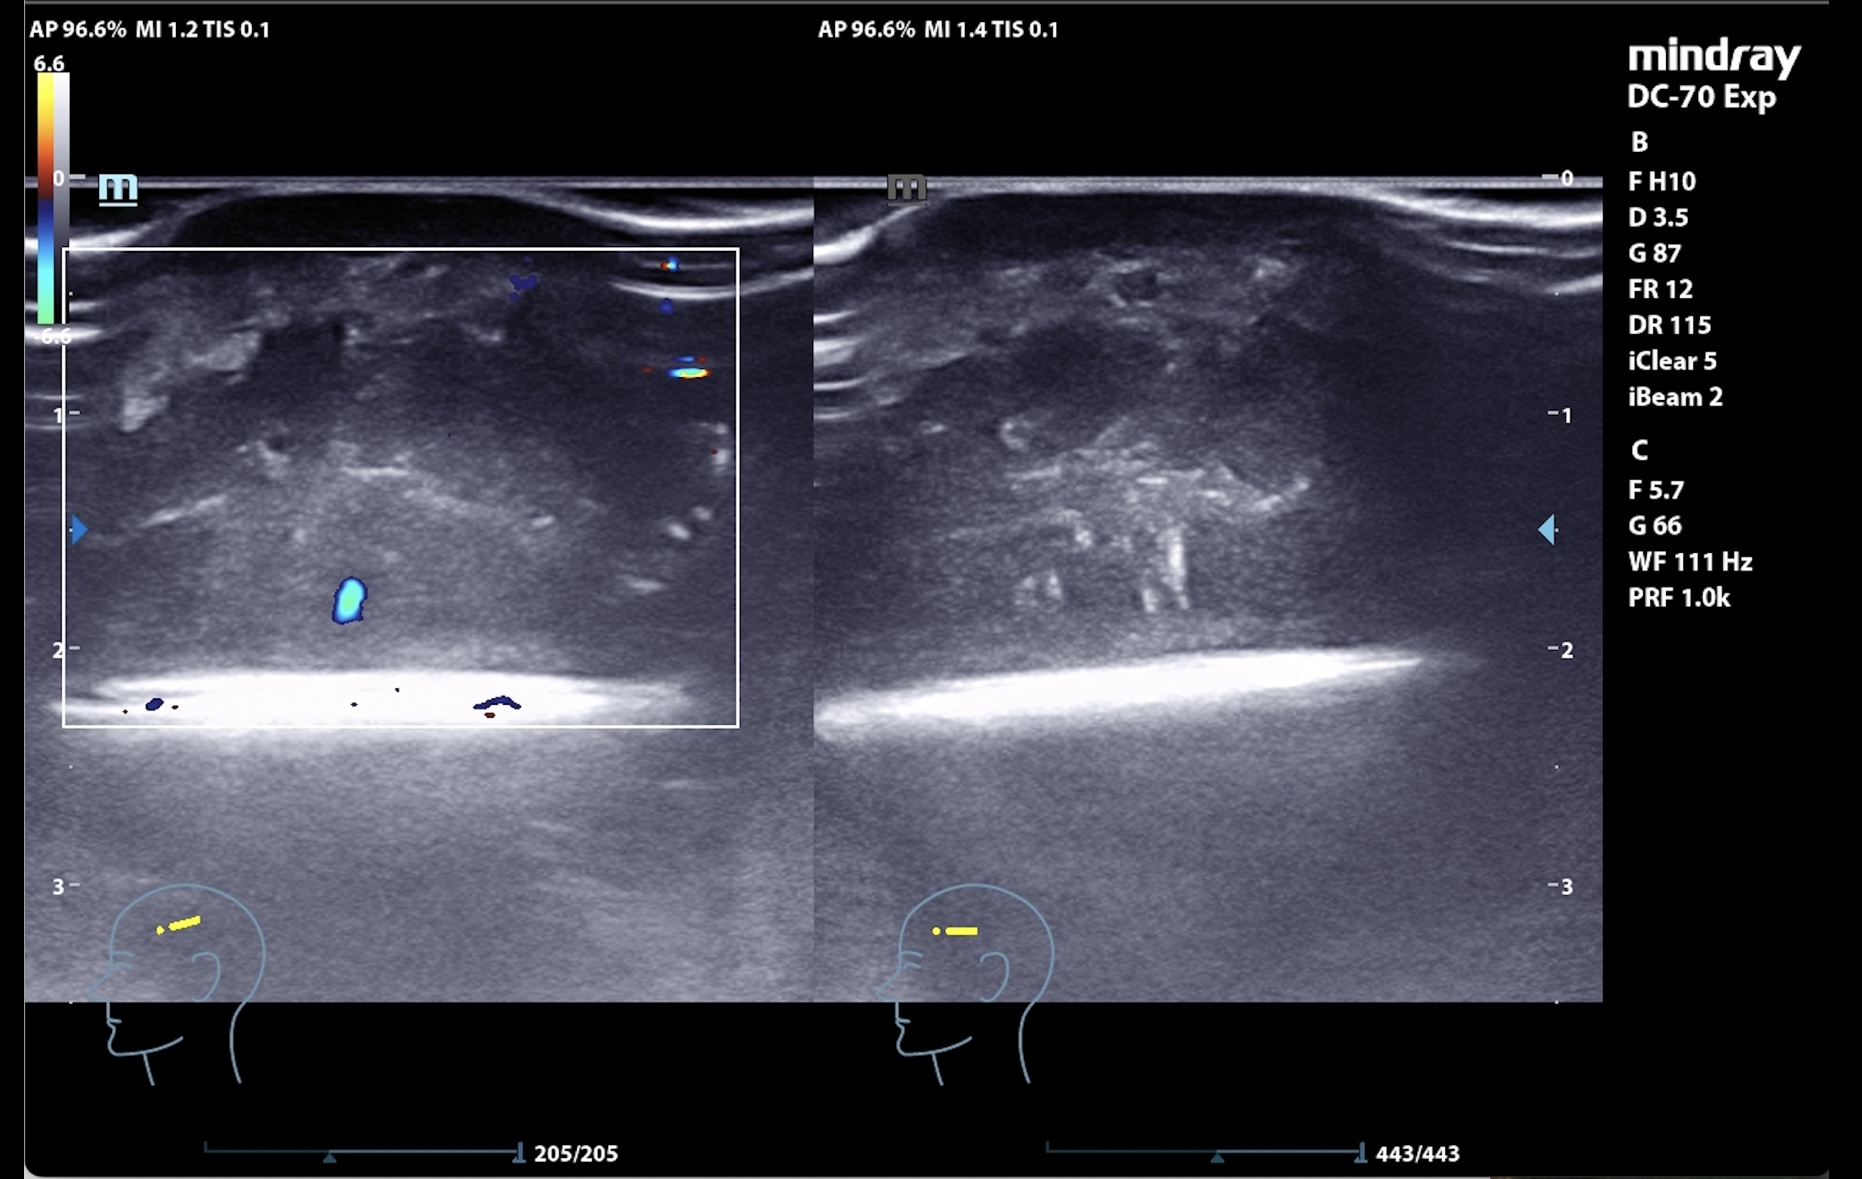

Se realiza en consulta ecografía, donde, para evitar la contaminación, se utiliza una funda estéril con gel conductor en su interior y clorhexidina entre la sonda y el cuero cabelludo como conductor líquido.

La imagen muestra una lesión heterogénea, con bordes netos, pero sin cápsula, microcalcificaciones en su interior y zonas hipoanecogénicas de necrosis líquida interna, así como vascularización interna intensa en Doppler. El patrón sugería proceso infiltrativo, por lo que se priorizó derivación urgente a dermatología.